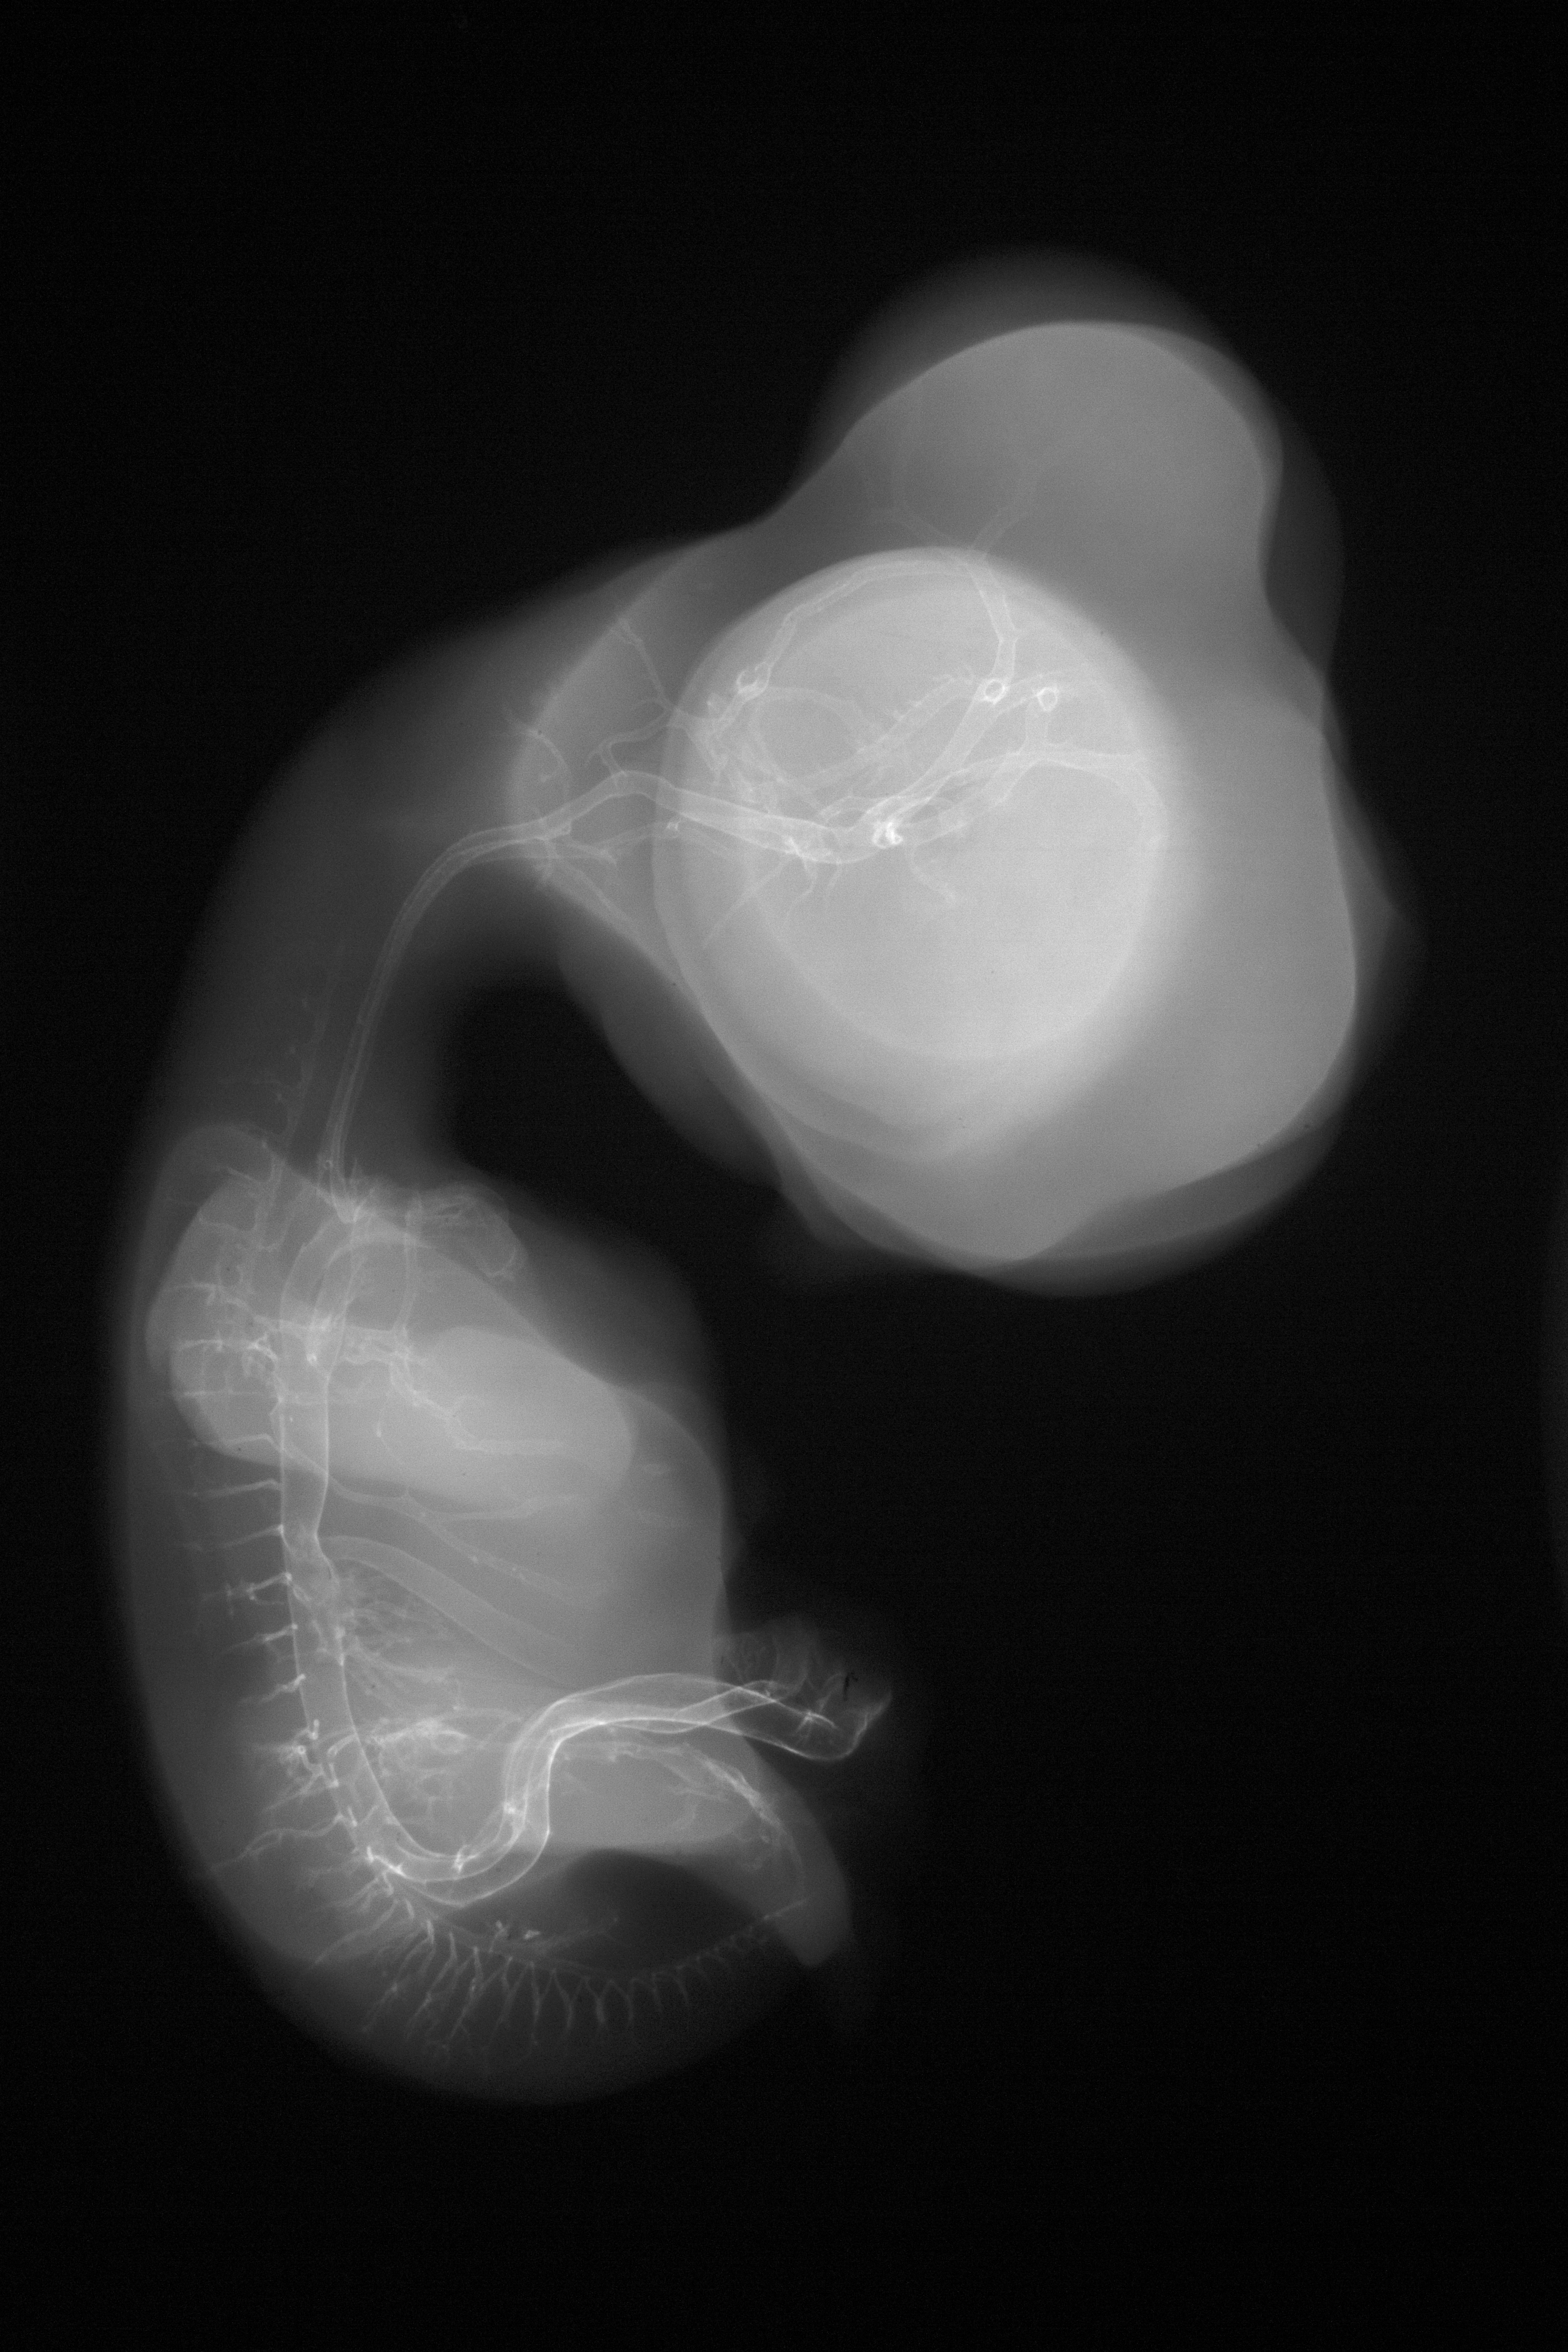

Chick Embryo Microangiography

Hamburger-Hamilton (HH) Stage 30 (approx. 6.5 days)

X-Ray Micrographs